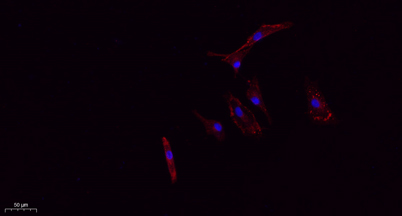

CD63 rabbit pAb

Product name: CD63 rabbit pAb

Dilutions: IF: 1:50-200 Western Blot: 1/500 - 1/2000. IHC-p: 1:100-1:300. ELISA: 1/20000. Not yet tested in other applications.